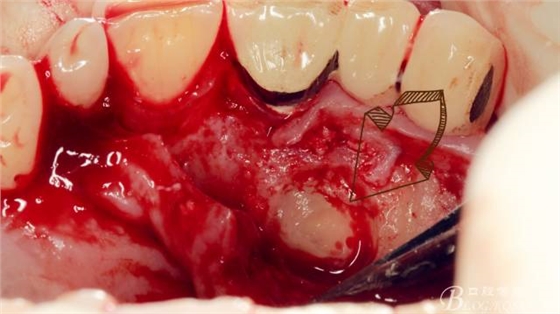

長柄裂鉆分離牙冠,微創(chuàng)挺插入后順時(shí)針或者逆時(shí)針輕擰一下,手上去感受牙冠斷開的那一瞬間,有時(shí)候耳朵也能聽見啪得一聲,不過此刻因?yàn)檠拦谥車墓亲枇?,牙冠是不能取出的?p style="text-align: left;">

T形分牙,把牙冠分為兩瓣,減少阻力。

分別挺出兩瓣牙冠,可見牙根截?cái)嗝妗?p style="text-align: left;">